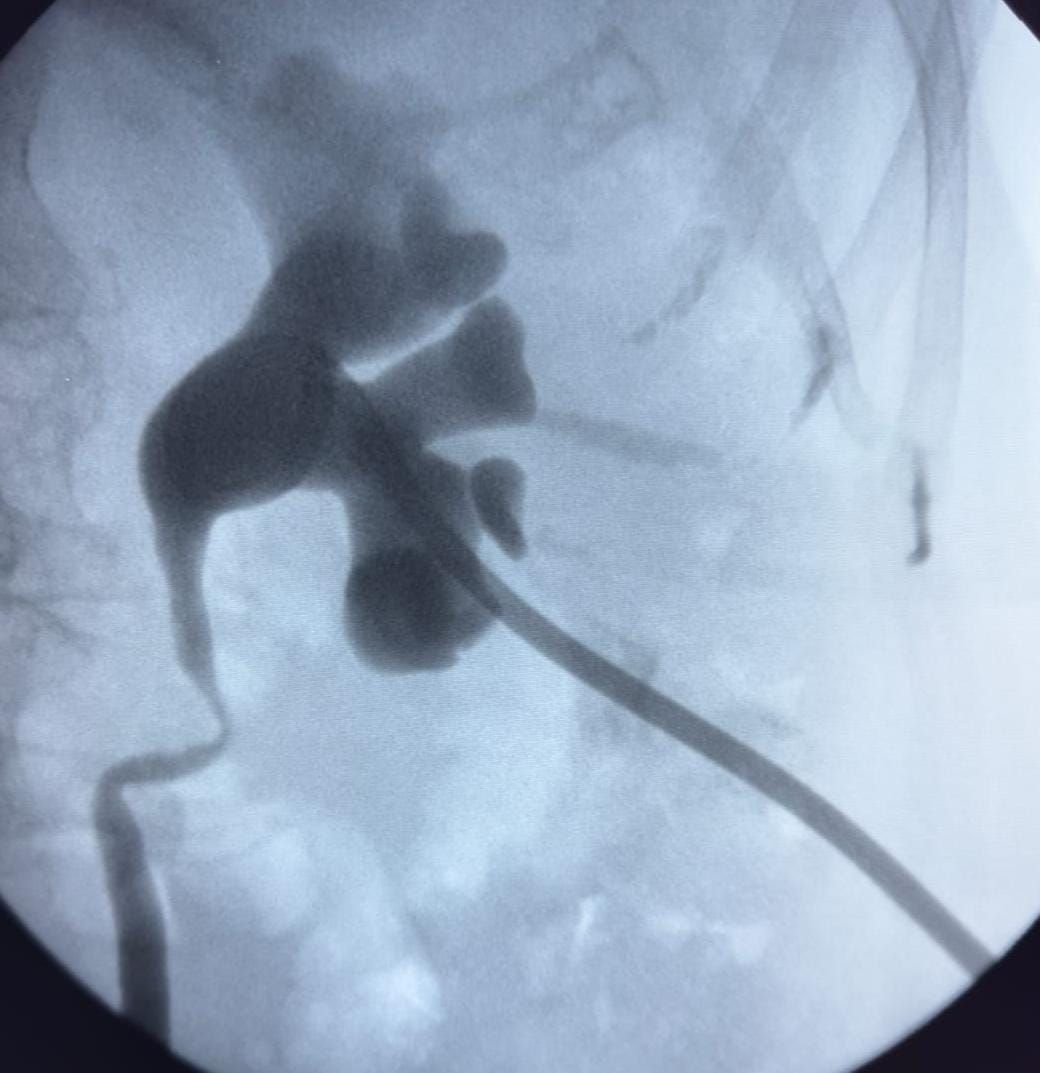

Originario del Estado de Hidalgo, egresado de la Licenciatura de Medicina de la Universidad Autónoma del Estado de Hidalgo. Cursé la Especialidad Médica en Imagenología Diagnóstica y Terapéutica en el Hospital General de México (2015-2019) y el Curso de Posgrado de Alta Especialidad Médica de Radiología Intervencionista Torácica Abdominal Vascular Periférica (2019-2020). Ocupé el cargo de Médico Radiólogo en hospitales privados como: Hospital Diomed y Hospital StarMédica Roma. Tuve el cargo de Médico Radiólogo de fines de semana en el Hospital General de México "Dr. Eduardo Liceaga" donde tuve la oportunidad de desarrollar y mejorar mi destreza para la evaluación de estudios especializados de Tomografía Computada, Ultrasonidos y Dopplers, con más de 6,000 estudios evaluados en un periodo de 2 años. Así como, Médico Adscrito del Servicio de Radiología Intervencionista del Hospital Juárez de México. Actualmente, formo parte del equipo multidisciplinario del Centro Oncológico de Alta Especialidad del Estado de Hidalgo, en el área de Radiología Intervencionista; encargado del diagnóstico y abordaje clínico en procedimientos mínimo invasivos. Estoy credencializado en diversos Hospitales Privados de prestigio en el Estado de Hidalgo y CDMX. Amplia experiencia en la realización de Estudios diagnósticos y terapéuticos: Ultrasonido Especializados (Abdomen, Genitourinario, Cuello, Tiroides, Doppler arterial y venoso periférico, Carotídeo). Biopsias guiadas por Ultrasonido y Tomografía Computada Drenaje de abscesos hepáticos y colecciones. Derivación biliar percutánea y Nefrostomías percutáneas. Terapia Endovascular y Ablación para el tratamiento de cáncer.